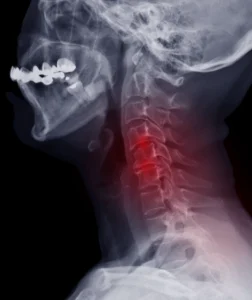

Servikal Miyelopati (Boyun Omuriliği): Boyun bölgesindeki omurların üzerine baskı yaparak omuriliği etkileyen bir durumdur. Genellikle yaşlanma ile birlikte omurgada oluşan değişikliklerden kaynaklanır, ancak travma da neden olabilir.

Omurgada meydana gelen dejenerasyon, özellikle yaşlı bireylerde miyelopatiyi tetikleyebilir. Omurlar arasındaki disklerin zamanla yıpranması ve omurga kanalının daralması (spinal stenoz), omuriliğe baskı yaparak miyelopatiye yol açabilir. Bu durum genellikle servikal miyelopati ile ilişkilidir.

Omurga diskleri, omurlar arasındaki yastıklar gibi işlev görür. Bu diskler yerinden kayarsa veya yırtılırsa, omuriliğe baskı yapabilir ve miyelopatiye yol açabilir. Disk kaymaları, genellikle bel veya boyun bölgesindeki omurlar arasında meydana gelir.